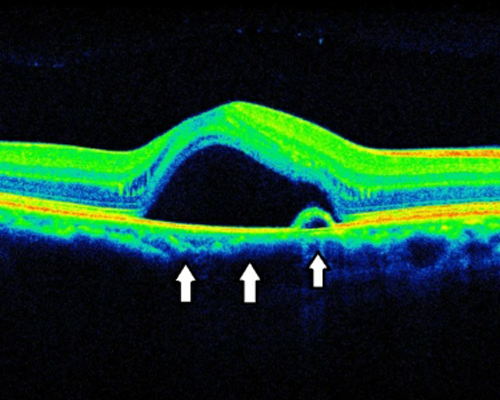

황반주름이란 황반 위에 딱딱한 섬유성 막이 자라나는 질환으로 물체가 휘어 보이거나 서서히 시력이 떨어지는 질환입니다.

황반부에 생긴 신생혈관

막이 황반부를 위로 잡아당겨 전반적인 두께가 증가하고 구조가 뒤틀림

적절한 시기에 수술을 하면 예후가 좋으나, 증상이 악화된 후에는 회복이 어렵습니다. 따라서, 수술 시기를 놓치지 않도록 주의해야 합니다.